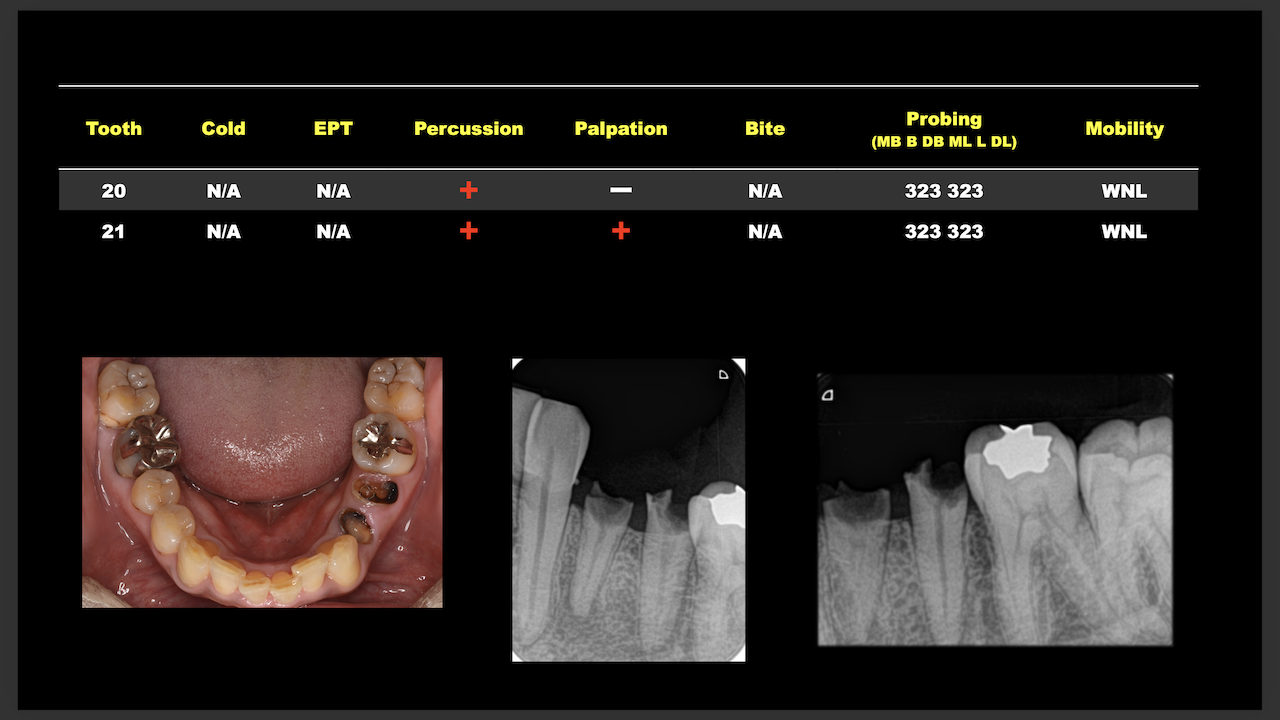

次は東京から参加のN先生。

術前/術後を比較した。

#29

#4

ラバーダム防湿をして行った根管治療の威力がわかったと思う。

素晴らしいケースだ。

これからもこのまま続けていけば実力は向上します。

頑張ってください。

次はN先生と同一法人のF先生。

#10のRCTと3M recallである。

#9,10と病変があるが、

#9はColdに2秒で反応し、その痛みが5秒でおさまったことから生活歯と判断し、

Cold, EPTに反応がなく打診痛もある#10を患歯と考え、#10のみ根管治療することとなった。

その際の成功率は86%である。

と術前に患者さんに告げて治療へ導入し以下のようになった。

3ヶ月しか経過していないが根尖病変は大きく減少した。

治療していない#9には変化があまりないがだからと言って手をつける必要性はない。

患者に症状がないからだ。

先生も診断の重要性を学ばれたと思います。

これからも頑張ってください。